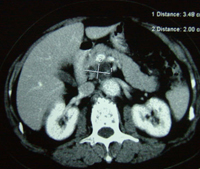

黄先生告诉记者:2004年7月初,他大便次数增多,腹部隐隐不适,去江门市人民医院检查,做B超和CT,发现胰腺肿癌。突然的打击几乎让他精神崩溃。黄先生的太太是护士,对胰腺癌的严重性早有所闻。有医生劝黄先生接受手术,但全家反对,一方面黄先生年事已高,另一方面他们了解胰腺癌能切除者微乎其微。一位邻居告诉他们:广州复大肿瘤医院有不开刀的冷冻治疗,对肝癌、肺癌等许多肿瘤有良好效果。7月14日,夫妻俩带着简单的行李,直奔广州,当日住进复大肿瘤医院。牛立志博士等医务人员给黄先生作了详细检查,作了肿瘤活检,确诊为胰腺囊腺癌。7月16日,黄先生接受了冷冻加125-碘粒子植入治疗。医生在CT引导下,作腹部穿刺,不开刀,将细针直接插入胰腺肿瘤内,先冷冻,再植入125碘粒子20粒。第二天,黄先生下地行走;第三天,恢复正常饮食;第八天,出院回家。三年来,除腿关节有点老年退化性变性外,他生活完全正常,无疼痛,食欲好,睡得香,每天散步半小时。CT复查显示:胰内肿瘤消失。

黄先生胰腺癌治疗前后CT:A 治疗前,B 治疗后3个月,C 治疗后 12个月